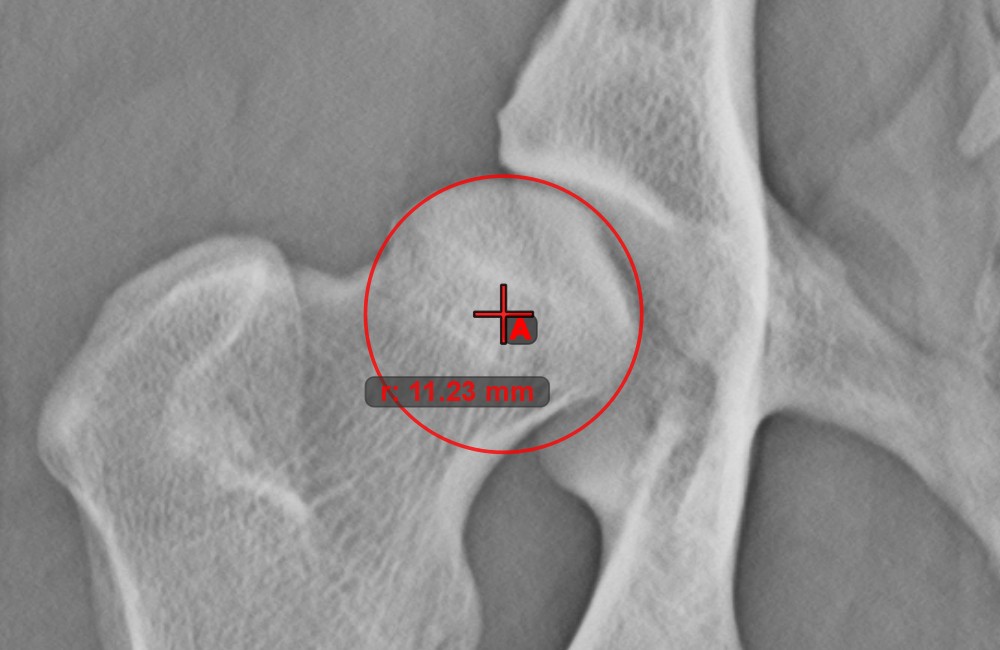

Kör 3 pontból¶

Kezdje az eszköz kiválasztásával a bal oldali eszköztárból, és rendelje hozzá az egyik elérhető egérgombhoz. Helyezze el a kör három pontját, vagy válassza ki a pontokat a jelenetben már meglévők közül. A kör automatikusan létrejön a három pont elhelyezkedése alapján. A kör origója mindig O betűvel lesz jelölve. A kör sugara automatikusan kiszámításra kerül.

Módosítsa a három pont helyzetét a kör sugarának megváltoztatásához a Elem kiválasztása/mozgatása eszközzel.